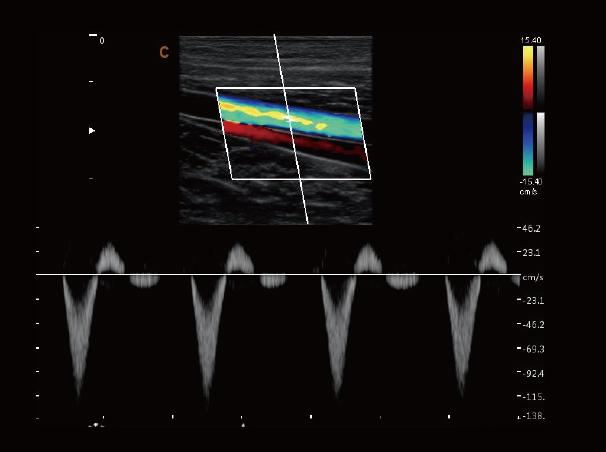

血管,频谱模式